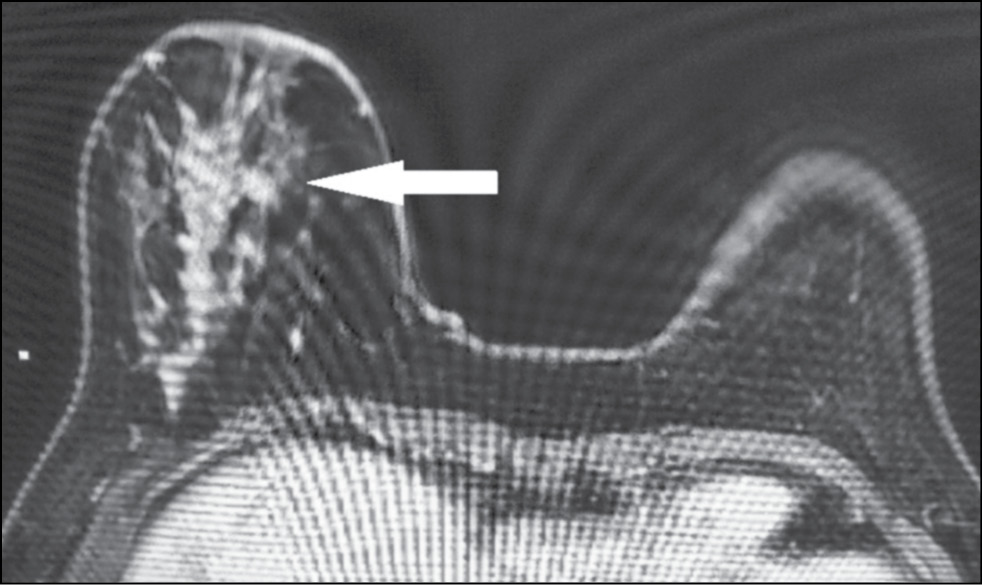

A 59-year-old patient complained of erosive changes in the nipple (Fig. 1). Physical examination revealed erythema, erosion, and nipple retraction. Doppler ultrasonography with color flow mapping revealed increased blood flow in the nipple projection (Fig. 2). Mammography findings were normal. To assess the extent of disease spread, breast MRI with contrast enhancement was performed. The early postcontrast series (Fig. 3) and maximum intensity projection (MIP) images (Fig. 4) showed a segmental contrast retroareolar area from the nipple level to posterior breast sections. Ultrasound-guided core biopsy followed by immunohistochemical analysis revealed Paget’s disease of the nipple with high-grade intraductal carcinoma in situ. Receptors for estrogen (G3 ER) and progesterone (PR) were negative. Oncogenic protein Ki-67 was 45%.

Figure 4. Magnetic resonance imaging of Paget’s disease (maximum intensity projection): the retroareolar area of segmental enhancement from the nipple level to the posterior breast (arrow).

In 22%–71% of cases, mammography provides a false-negative result [21], and in this case, breast MRI is indicated to identify abnormalities and deter the extent of disease spread. [20] Characteristic MRI findings include asymmetry, thickening, flattening, retraction of the NAC, and uneven contrast accumulation in this area. MRI allows evaluating adjacent structures and axillary lymph nodes.